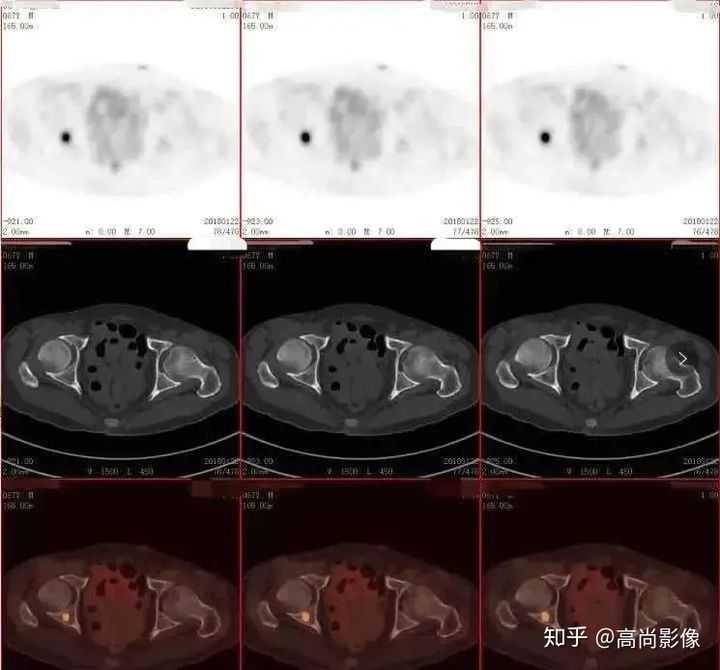

1年多來,黃大爺?shù)碾p手總是抖個不停,他和家人都非常擔(dān)心。黃大爺來到中心進(jìn)行了PET/CT的檢查,檢查發(fā)現(xiàn),黃大爺?shù)亩喟桶忿D(zhuǎn)運體顯像基本正常,最后,黃大爺被診斷為良性震顫。

雙側(cè)尾狀核、殼核多巴胺轉(zhuǎn)運體分布對稱、均勻

相比之下,童大媽就沒有這么幸運了。除了右邊身子總是抖動,童大媽還有嗅覺障礙、動作緩慢等癥狀。童大媽的PET/CT檢查結(jié)果符合帕金森的表現(xiàn),為臨床診斷提供了重要依據(jù)。

雙側(cè)尾狀核多巴胺轉(zhuǎn)運體分布對稱,左側(cè)殼核后部多巴胺轉(zhuǎn)運體分布較對側(cè)明顯減少,結(jié)合童大媽癥狀,先考慮帕金森。